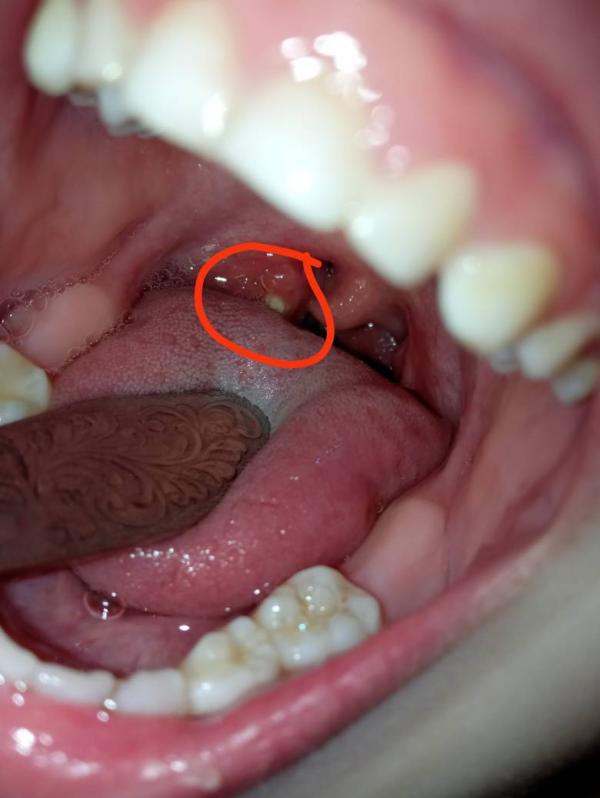

Что это за белая фигневина у сына в горле? Это ее еще чуть чуть видно, языком закрыто, там прям будто нарост небольшой или что.. Не болеет, не кашляет, никаких симптомов...

Это казеозная пробка на миндалинах) у дочи такие часто появлялись раньше, ходили к лору вымывать.

У нас такая, лор сказал на ручную промывку миндалин походить.

@nadiasweetma, да, верно. Мы как раз скоро запишемся на первую процедуру, лор будет определять сколько раз нужно промывать. Еще мне лор объяснила, что хоть мы и видим казалось бы всего одну пробку, но поглубже их там может быть больше. Как раз со мной был тот случай, пошла себе вымывать пробку и там из глубины еще повымывалось.

Это не страшно и не должно беспокоить. Такие гнойнички после перенесенной простуды бывают и потом миндалины самоочищаются, если вас это беспокоит, то пусть пополоскает горло фурацилином дней 5, выйдет быстрее, миндалины очистятся

Пробки миндальные. Мы такие выполаскивали раствором фурацилином.

Палочкой ватной убирала, на еще и воняет. Комочек гноя